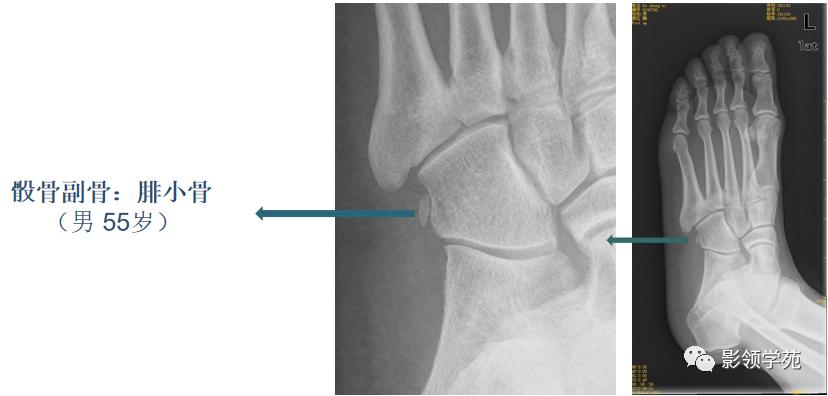

副骨

副骨是由于某一块骨的多个骨化中心在发育过程中没有融合、以致形成多出一块或几块的小骨,也可以是由一个额外的骨化中心发育而来。

三角骨是常见的变异,也被误称为距骨副骨。呈三角形, 与距骨后缘相切,三角骨与距骨后突外侧结节腓侧隐窝相对应。

-

三角骨可以成对存在,还可以与外侧结节融合,形成单一的突起,并可与距骨融合或形成关节。